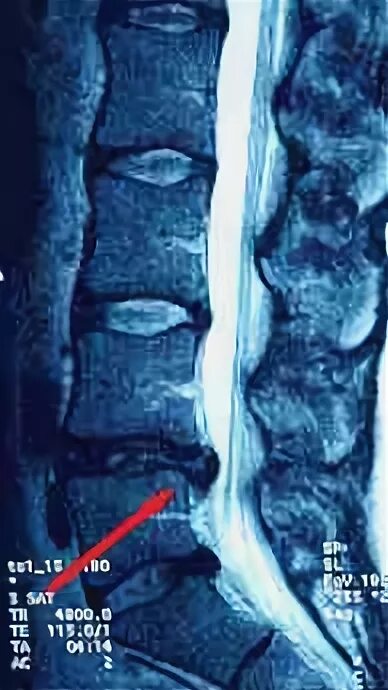

Грыжа позвоночника фото как выглядит поясничного отдела